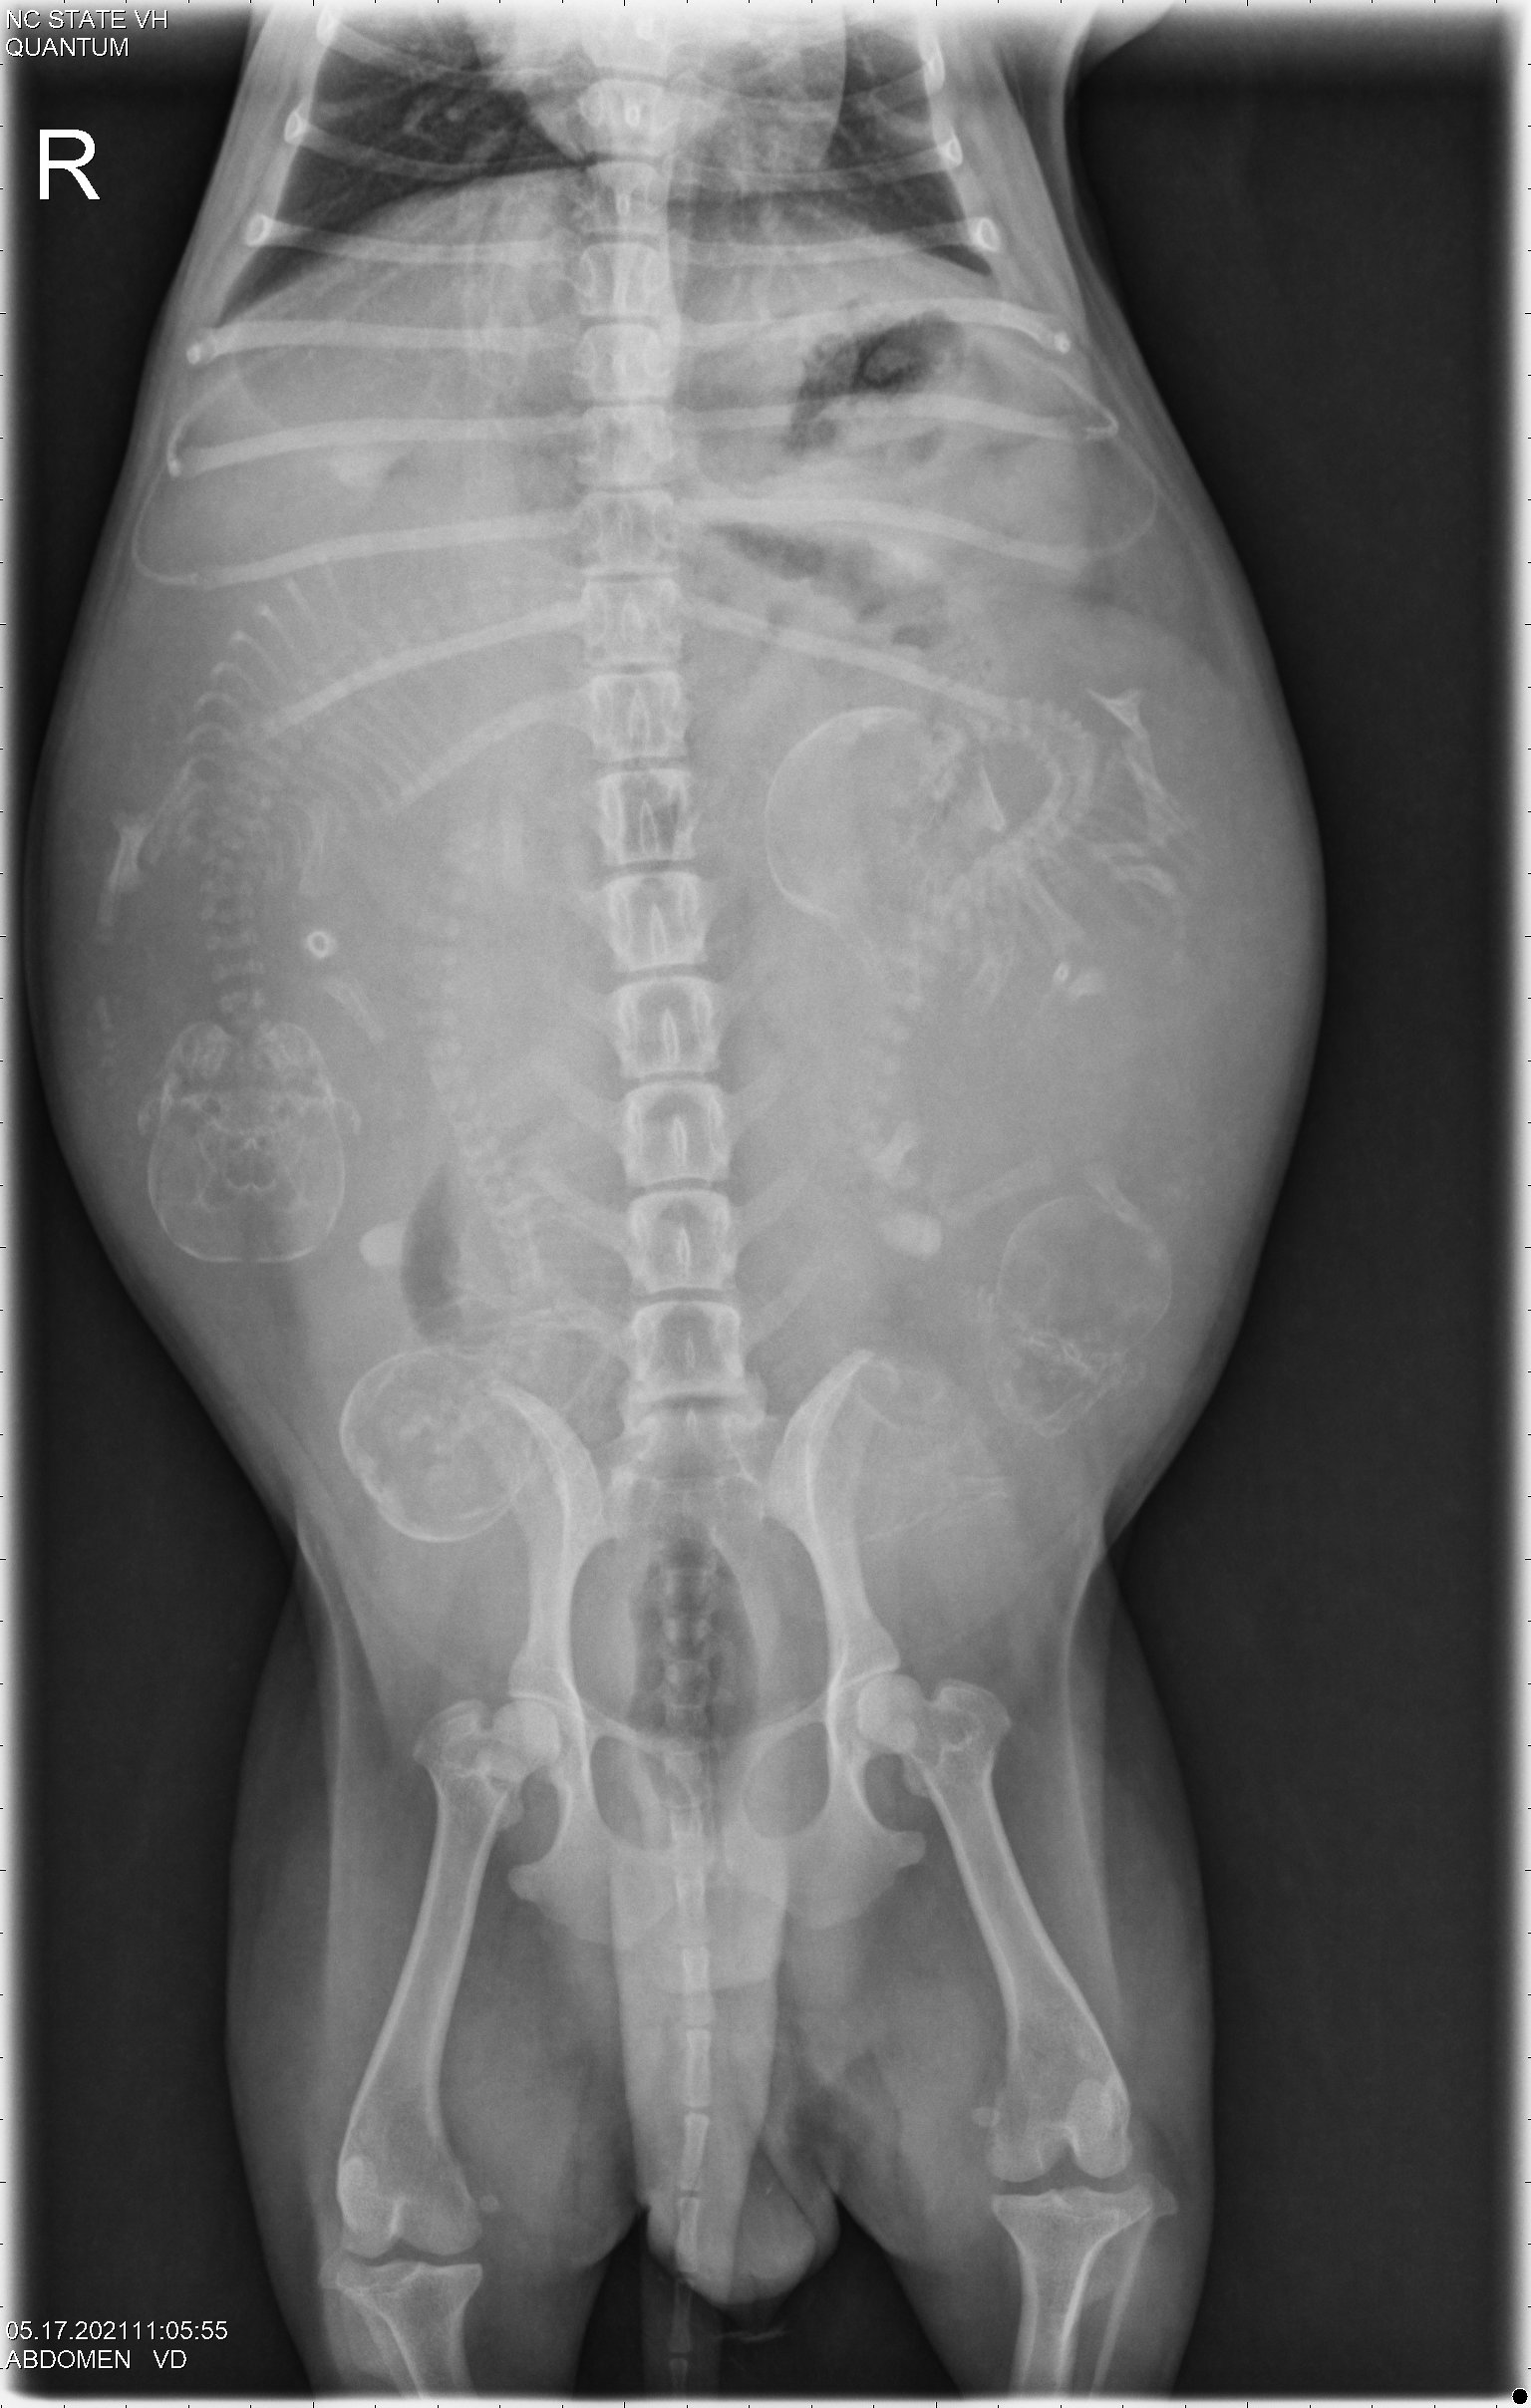

This morning we drove to NC State. X-rays (photo 1 and photo 2) confirmed that Siri has four puppies, and it looks like the puppies skulls are small enough that they will fit through Siri's pelvic canal. So trying for a free whelp is recommended. After taking the rest of my dogs to my petsitter, Siri and I moved into a hotel near the vet school.